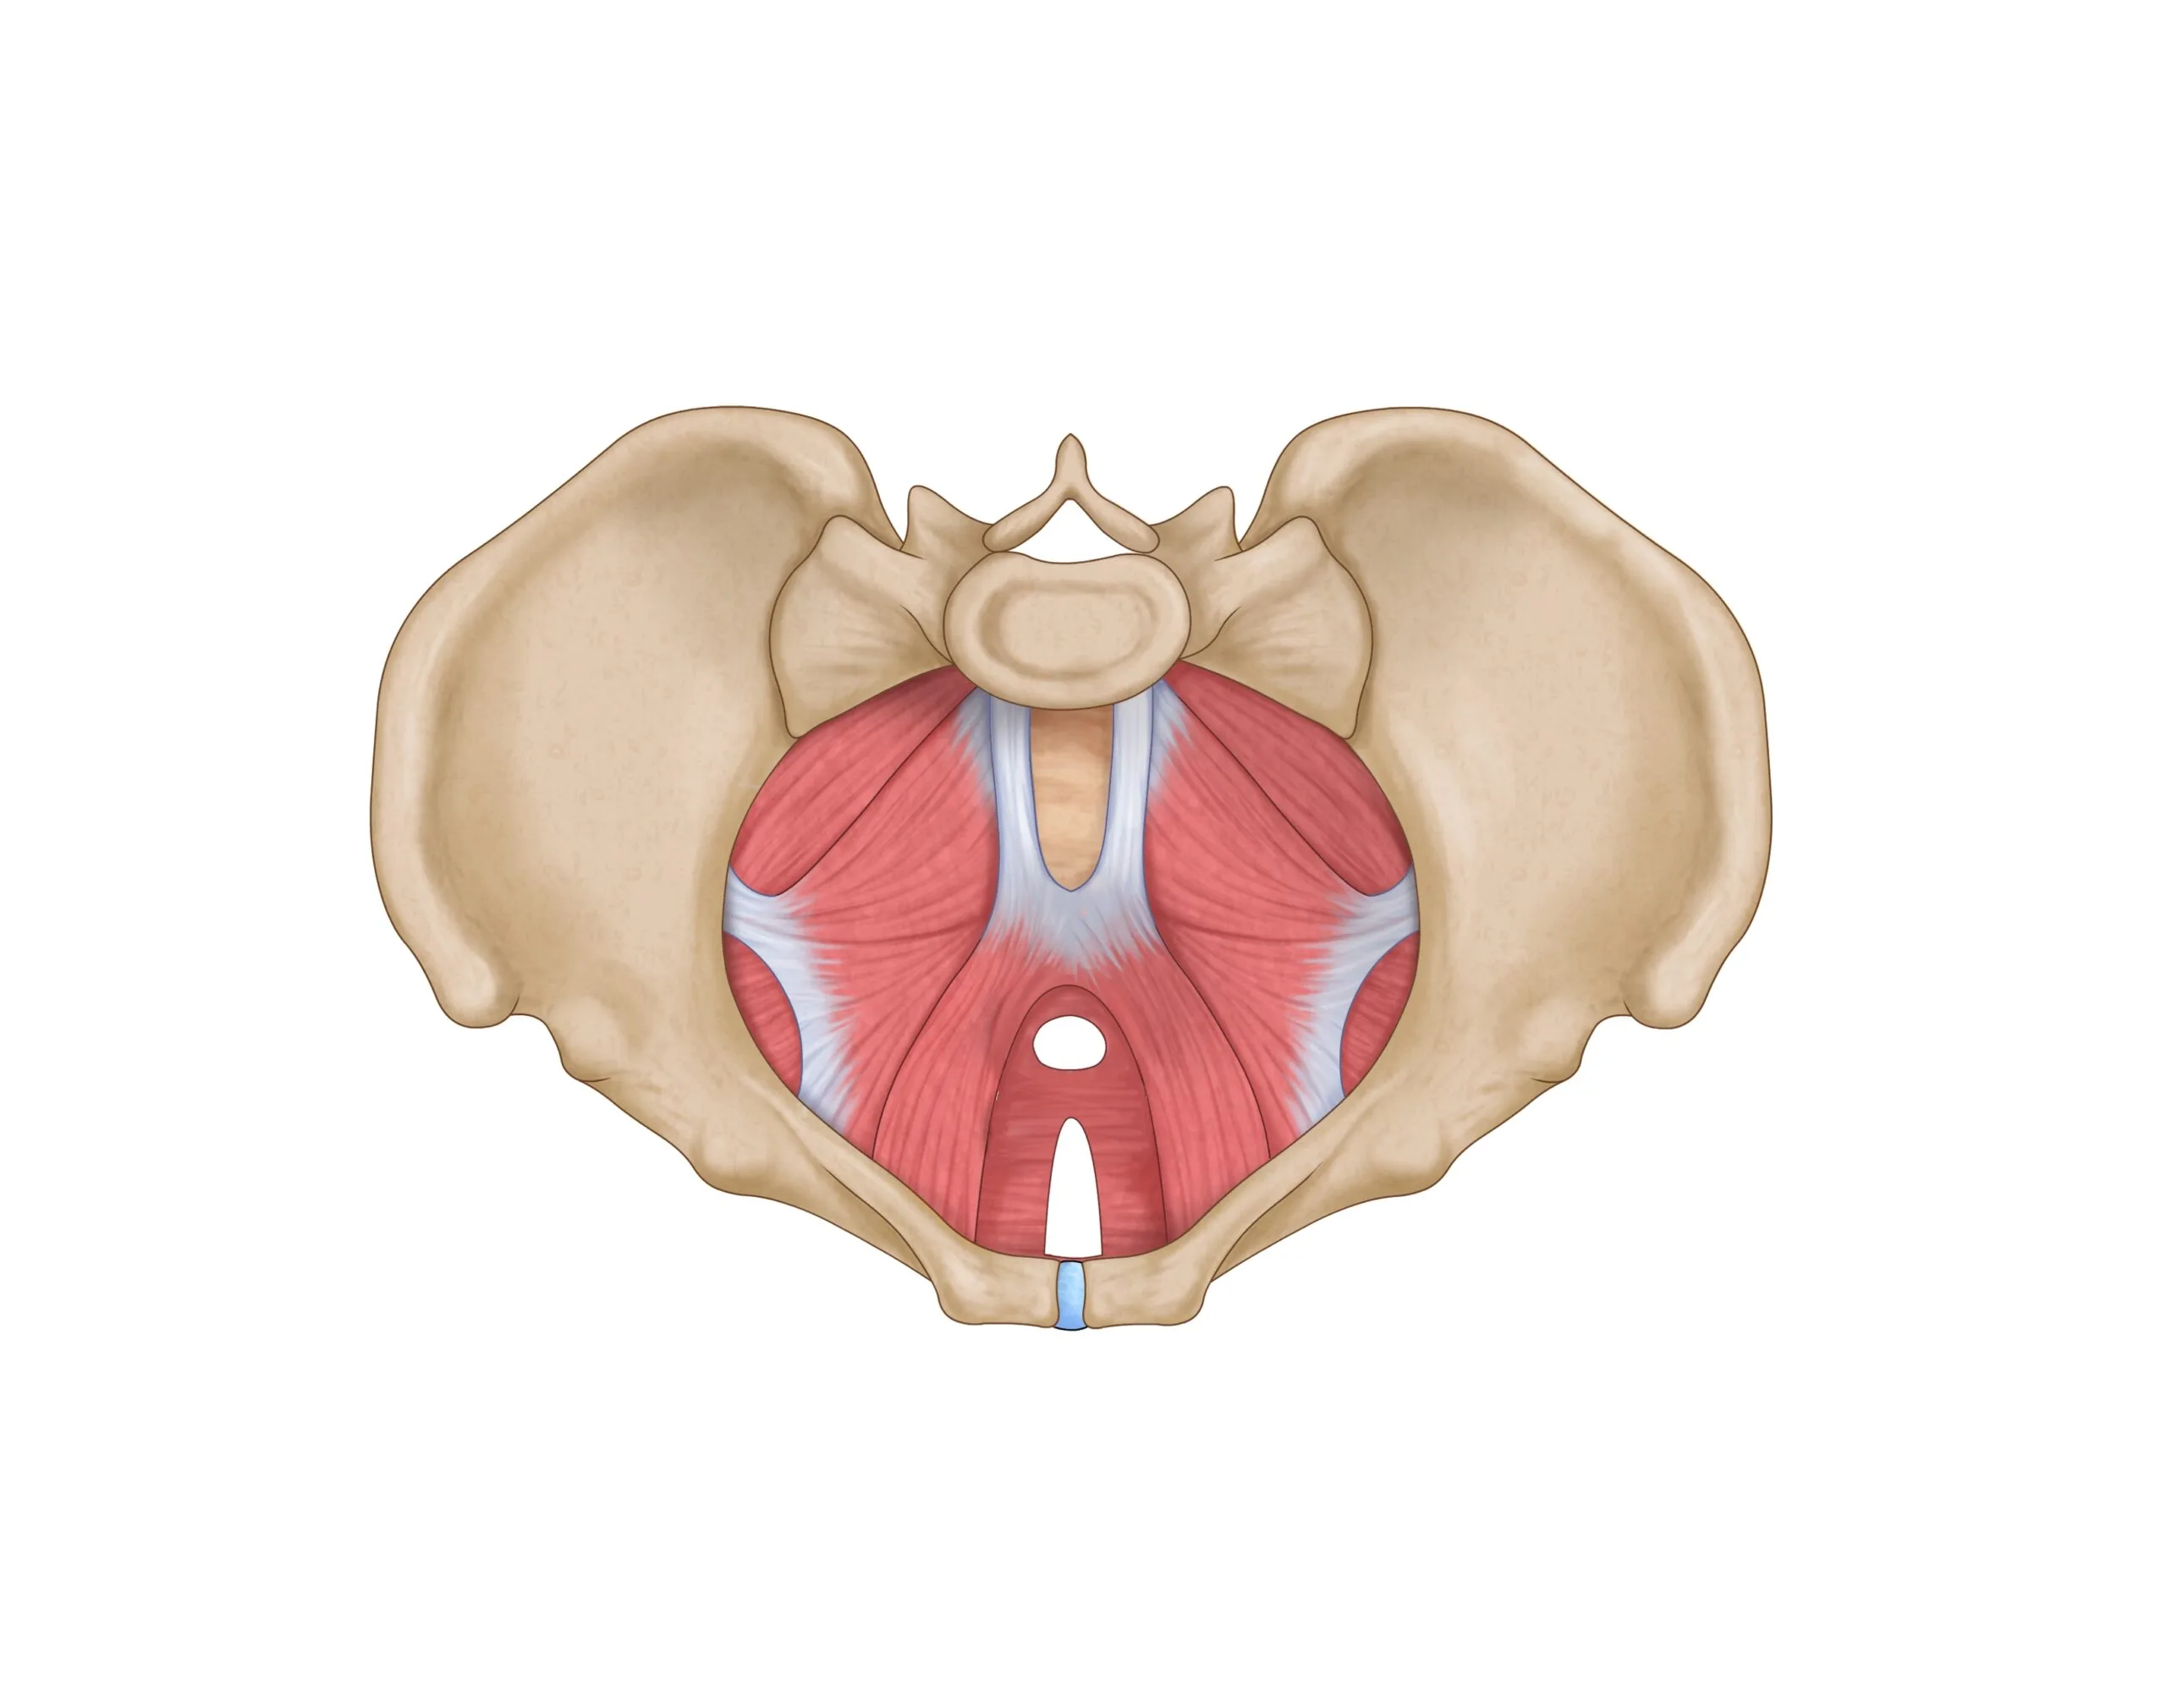

فیزیوتراپی کف لگن و هرچیزی که باید بدانید!

فیزیوتراپی کف لگن نوعی درمان برای مشکلات مربوط به کف لگن است. این درمان تخصصی شامل تمریناتی است که میتواند […]